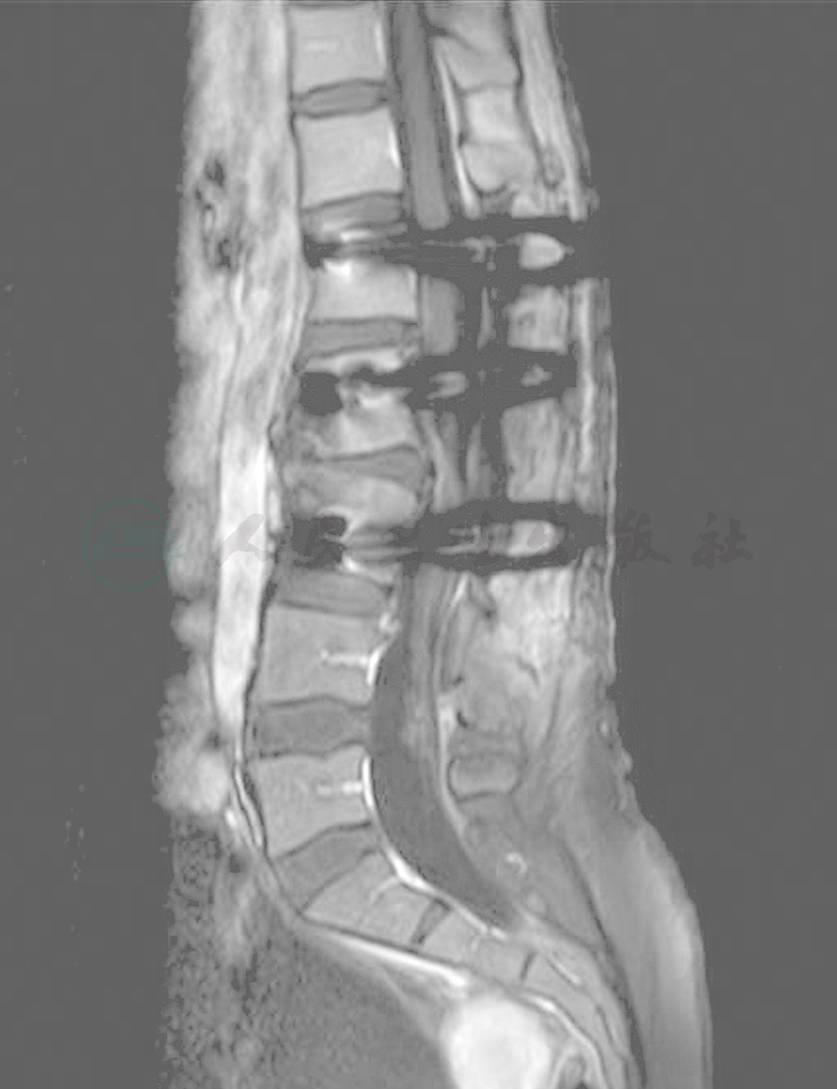

术后患者恢复良好,腰部疼痛基本缓解,右下肢麻木较术前明显减轻,四肢肌力、肌张力正常。复查CT及磁共振(MRI)示肿瘤切除彻底(图3),螺钉位置满意,脊柱曲度良好(图4、图5)。

图3 术后磁共振(MRI)

图4 术后CT

图5 术后三维重建